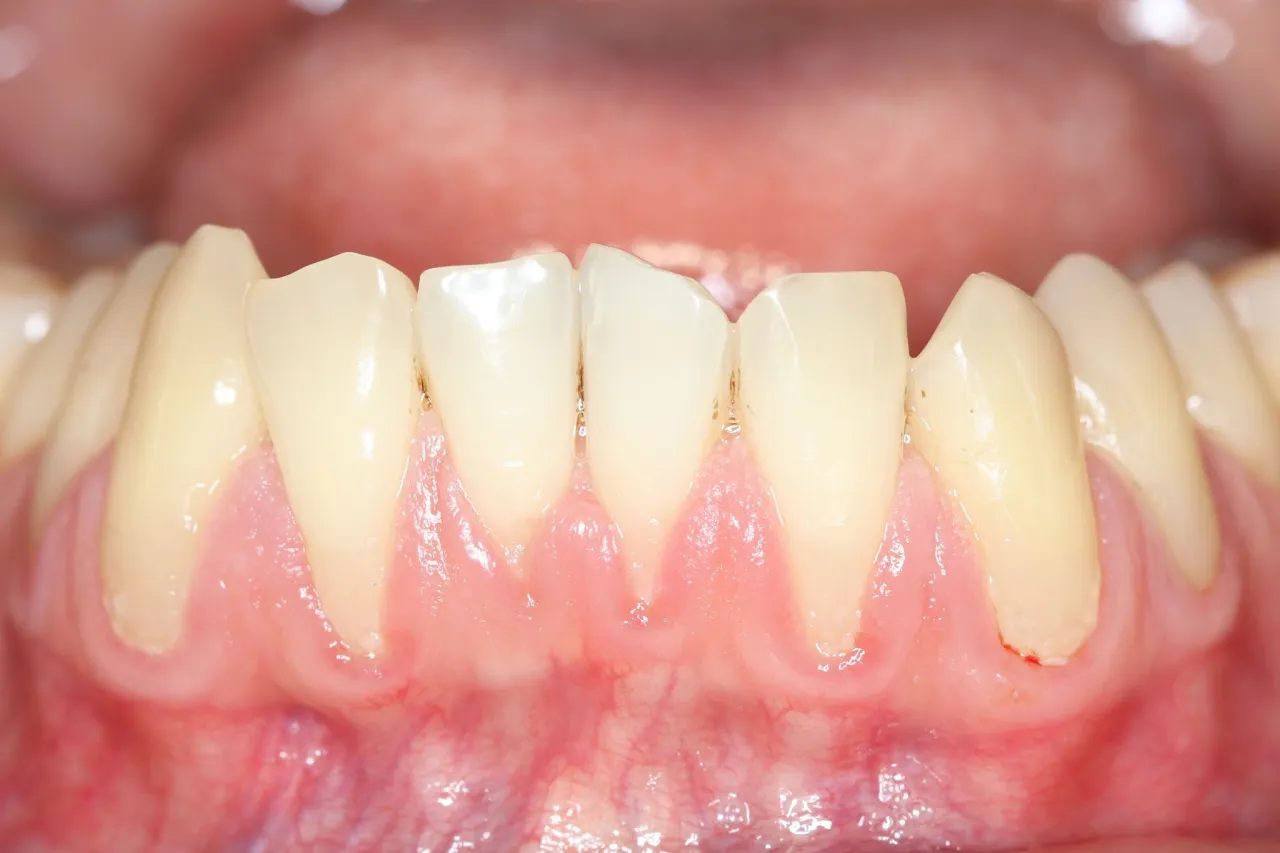

Zęby wydają się dłuższe: co wygląd dziąseł mówi o ich zdrowiu

Wizualne zmiany są często tym, co ostatecznie skłania pacjentów do wizyty u stomatologa. W przypadku recesji dziąseł zęby zaczynają optycznie wydawać się dłuższe niż dotychczas. Dzieje się tak, ponieważ obniżająca się linia dziąseł odsłania część korzenia, która normalnie jest ukryta. Możesz również zauważyć widoczne odsłonięcie żółtawej powierzchni korzenia zęba, która różni się kolorem od białej korony. Ta zmiana estetyczna jest bezpośrednim i niepokojącym skutkiem obniżenia linii dziąseł.

Nie tylko zdrowie: jak recesja wpływa na estetykę Twojego uśmiechu

Poza konsekwencjami zdrowotnymi, recesja dziąseł ma również znaczący wpływ na estetykę uśmiechu. Odsłonięte, optycznie "dłuższe" zęby, często z widocznymi, ciemniejszymi korzeniami, mogą wyglądać nieatrakcyjnie. Nierówna linia dziąseł, luki między zębami (tzw. "czarne trójkąty") oraz zmiana koloru zębów w okolicy szyjek mogą sprawić, że będziesz czuć się niekomfortowo, uśmiechając się czy rozmawiając.